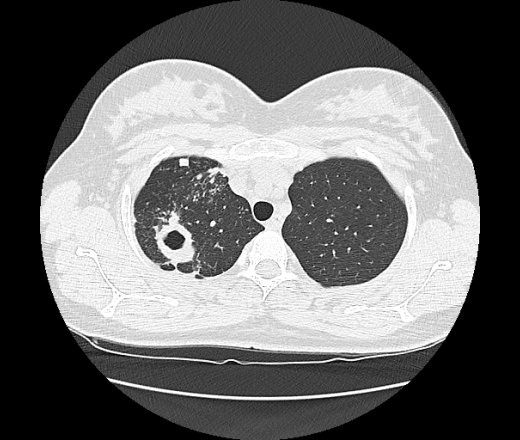

Ага, сначала вот эта с каверной пришла 12.05, а потом с туберкуломами 19.05 с интервалом в неделю, закон парных случаев, обе только родили, род.дом в панике, я в шоке

В том то и дело, что анамнез скудный, жалоб нет или врала, жила себе поживала девушка, забеременела, родила, а в правом легком "дырка".